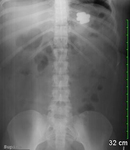

Radiografia abdominal simples revelando múltiplos corpos estranhos. Não há sinais de obstrução intestinal ou perfuração

De: Canda AE. BMJ Case Reports. 2009;2009:bcr12.2008.1354